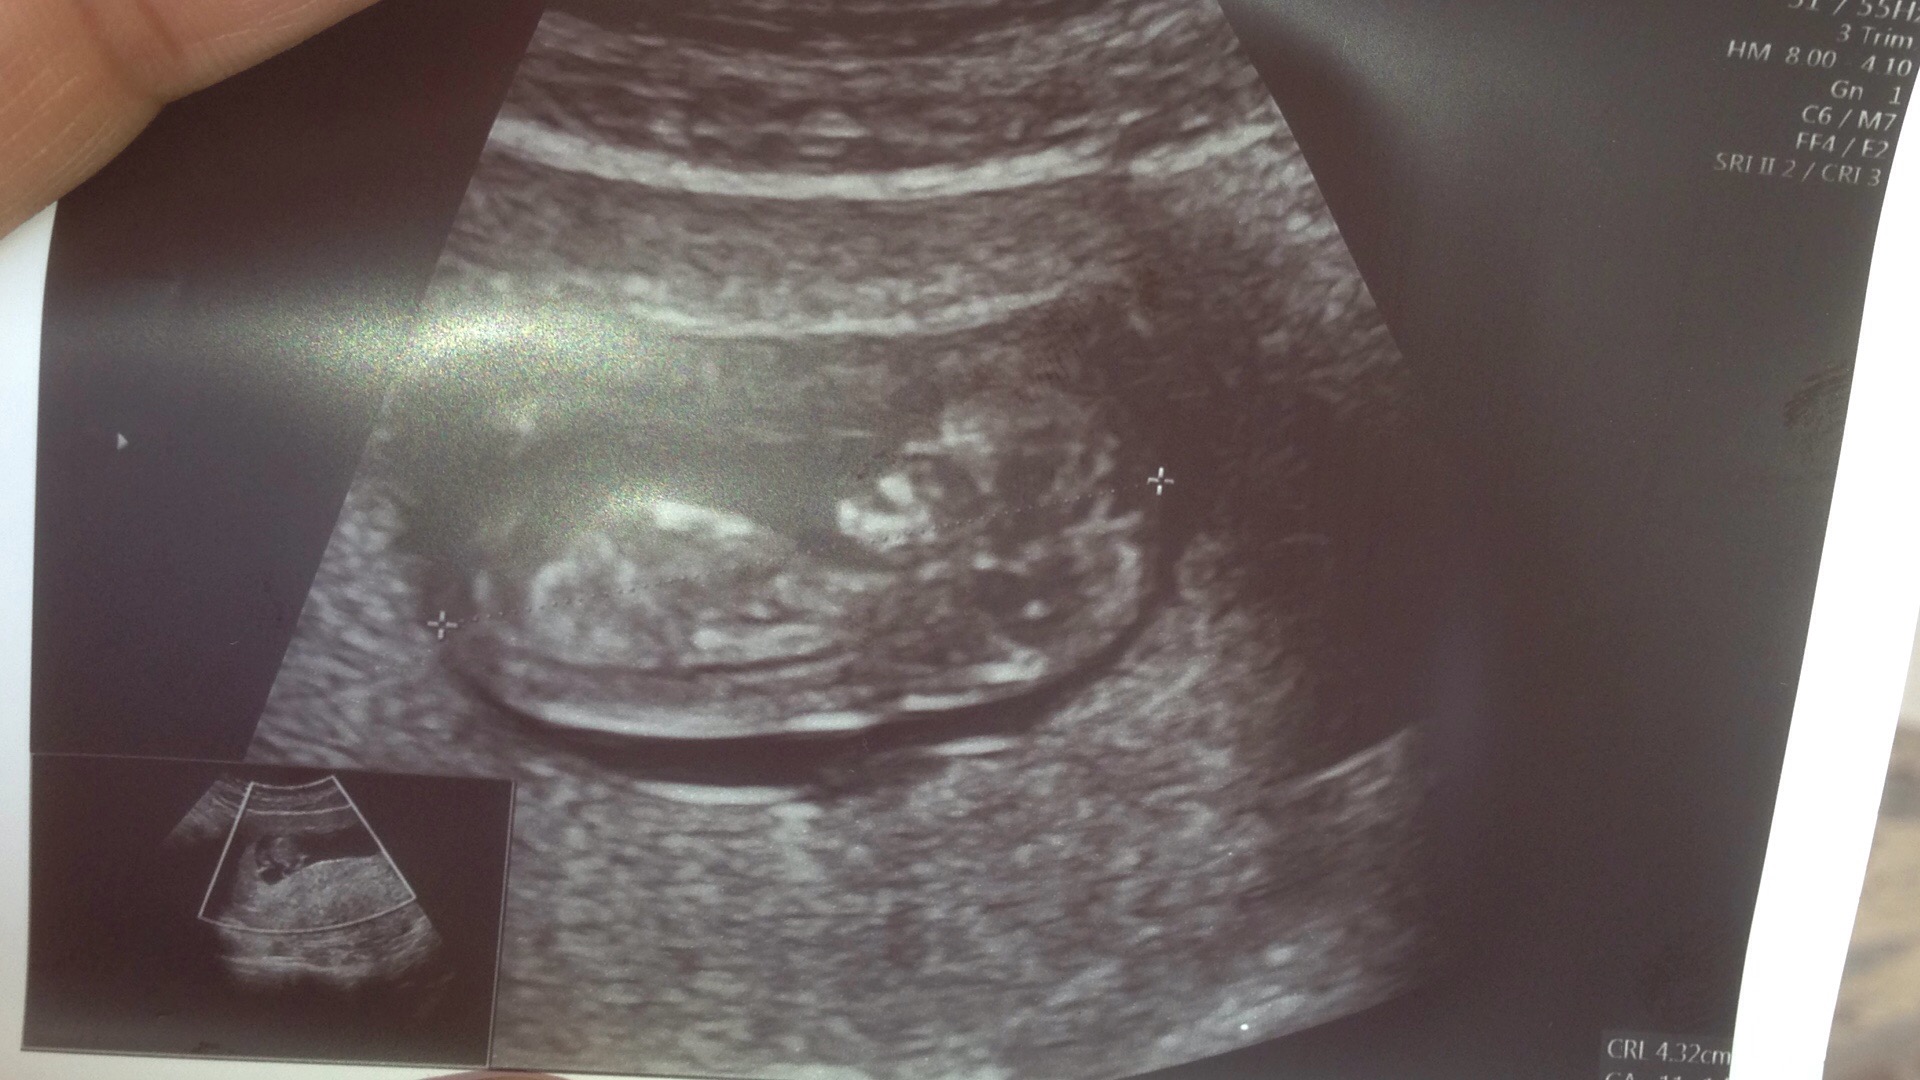

Cevabınız için çok teşekkür ederim sühan hanım.Daha net bir resim göndereyim.

• IMG_0244.JPG

IMG_0244.JPG

393,5 KB · Görüntüleme: 627